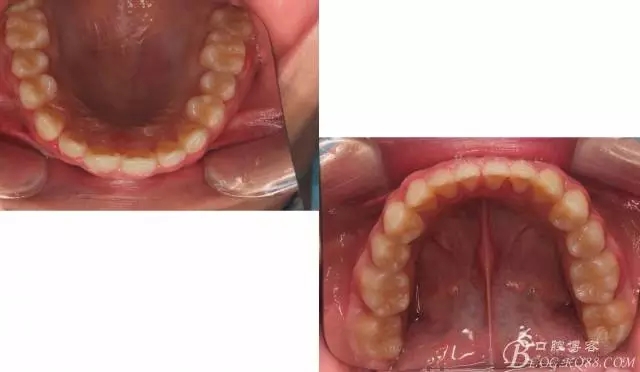

佩戴三個月的FR2, 效果奇佳!前牙基本達到淺覆蓋,淺覆合!接下來進入二期直絲弓固定正畸,排齊階段!

接下來盡管配合些雙側(cè)后牙對角牽引,咬合關(guān)系依,不盡人意。